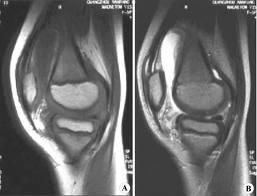

多數膝關節滑膜炎,是在上述各種膝關節損傷等情況下並發的,但也可以單獨發病或繼發於膝關節骨關節炎,後者多為老年人。在青壯年人多有急性膝關節外傷史,傷後膝關節開始發生輕度水腫、疼痛、活動受限及跛行。通常在傷後6---8小時出現滑膜反應性積液,膝關節明顯腫脹、發熱,不敢活動。檢查發現膝關節屈伸活動受限,下蹲困難並伴有疼痛,關節周圍可有局限性壓疼點,浮髕試驗陽性。慢性損傷性滑膜,可能無明顯外傷史,主要表現膝關節發軟及活動受限,腫脹持續不退,不敢下蹲。活動增多時加重,休息後減輕。久病者,可捫到膝關節囊肥厚感。對膝關節積液多者或反覆出現積液者,可做關節積液檢查,它能反應出滑膜炎的性質及其嚴重性。故關節穿刺和滑液檢查,對膝關節滑膜炎的診斷和鑑別診斷,均有重要參考價值。